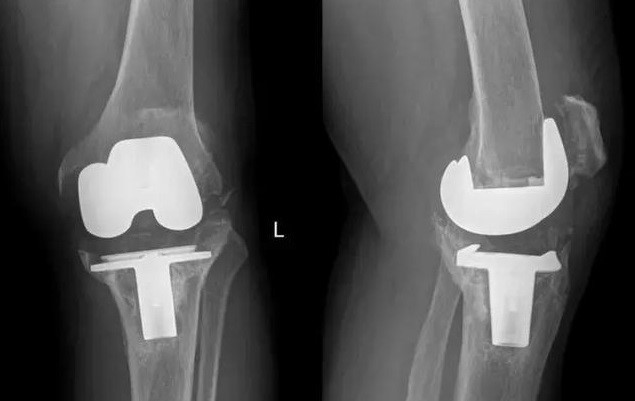

2017年11月,我國完成了全球首例個性化3D打印鉭金屬墊塊植入的全膝關(guān)節(jié)翻修手術(shù);2018年,LPW科技公司與環(huán)球先進金屬集團有限公司(GAM)宣布達成合作協(xié)議,圍繞金屬鉭的增材制造技術(shù)可為醫(yī)療外科、牙科、軍事、航空航天以及其他市場領(lǐng)域提供服務(wù)。鉭金屬通過3D打印制成的多孔鉭植入體,相較常見的多孔鈦植入物,具有更好的生物力學適配性、并具有接近人骨的彈性模量。在植入穩(wěn)定性上,具有較大優(yōu)勢。